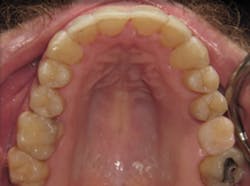

Case 1: 27-year-old male: 2-year clear aligner treatment. There was an estimated 8 mm to 10 mm increase in the transverse measurement. Case and photos courtesy of Dr. Daniel Noor.

Case 2: 48-year-old female: 15-month clear aligner treatment. This case demonstrates an improvement in a remodeled alveolar complex and an increase in vertical dimension. Case and photos courtesy of Dr. Ben Miraglia.

Before: V-shaped arch. After: U-shaped arch.

Before: V-shaped arch. After: U-shaped arch; implant placed No. 14.